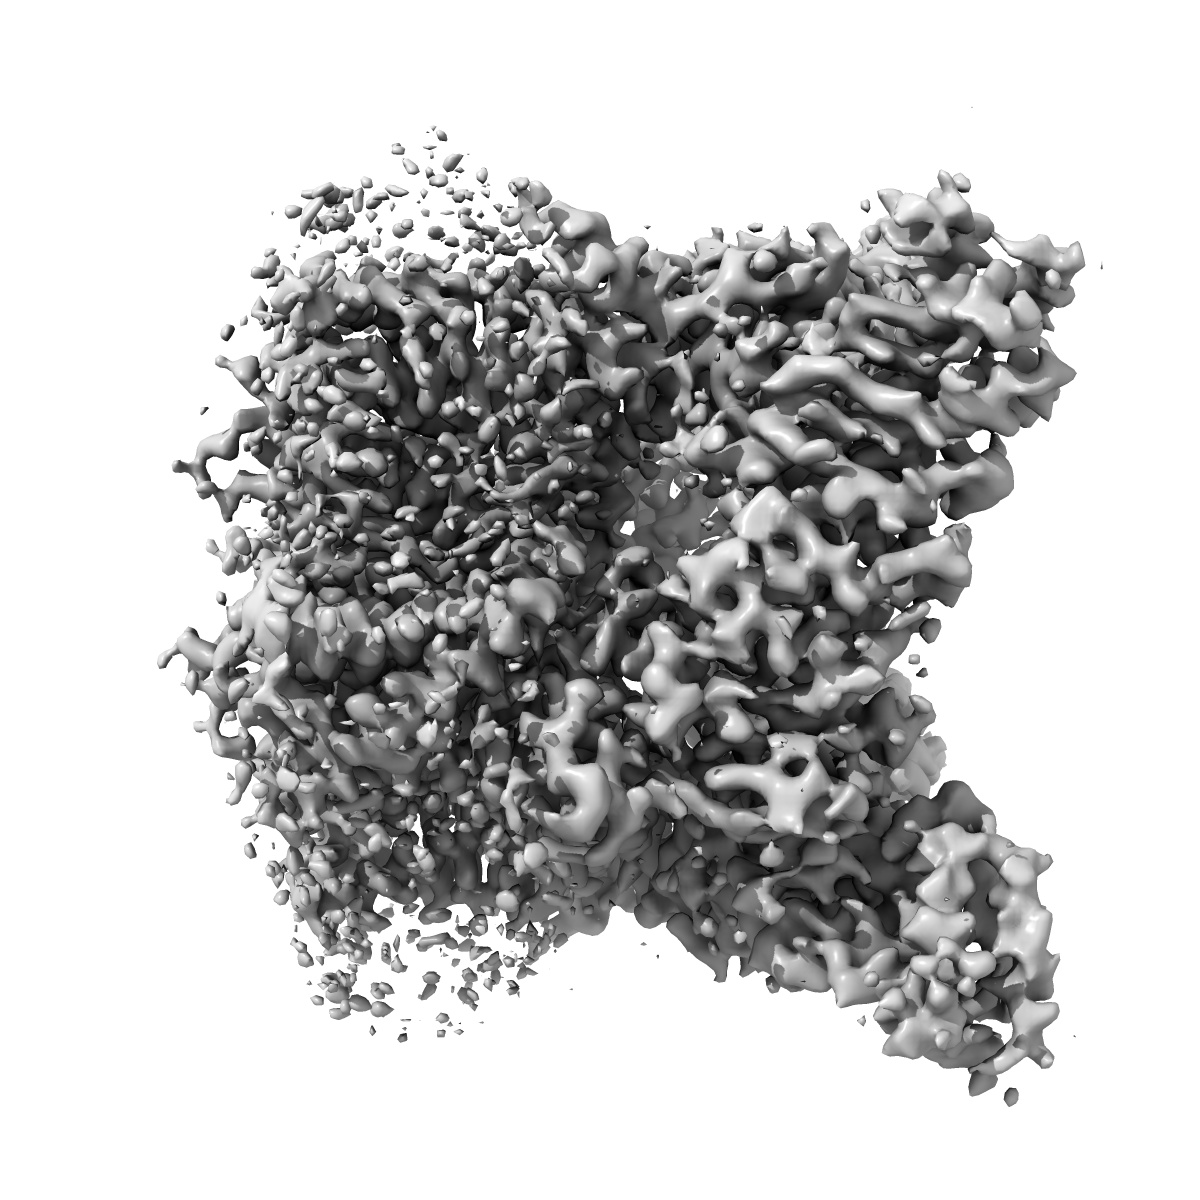

Inactivated-state cryo-EM structure of human TRPV3 in presence of tetrahydrocannabivarin (THCV) in cNW30 nanodiscs

Single-particle3.63 Å

Sample: full-length human TRPV3 in complex with THCV

Fitted models: 8v6m